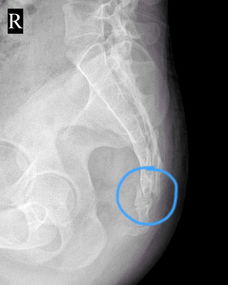

一抬臀部尾骨疼